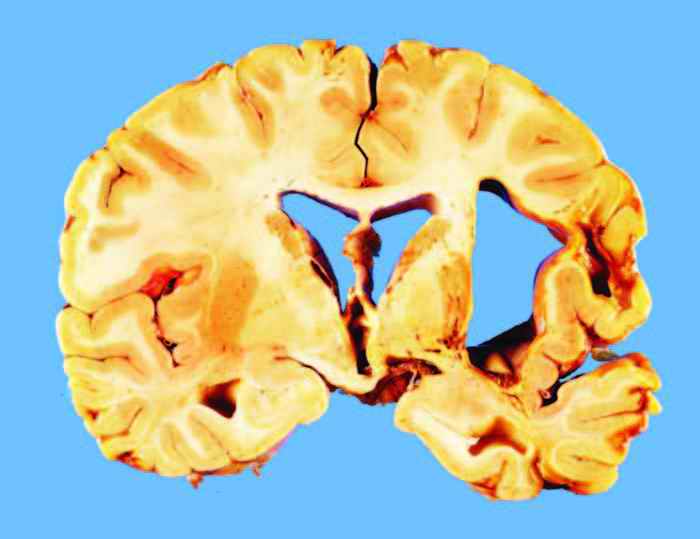

In so-called lateral ganglionic hemorrhage, as illustrated in Figures 3.7 and 3.8, the site of origin of the hemorrhage appears to be within either the external globus pallidus, the putamen, or the external capsule-claustrum, deep to the insula. The hemorrhage then appears to push the remaining basal ganglia toward the midline and then to dissect upward along the path of least resistance, through the white matter over the caudate nucleus, into the lateral ventricle, or to dissect forward or backward until another ventricular chamber is reached. Occasionally, the primary hemorrhage may occur within the internal capsule or thalamus and rupture directly into the lateral ventricle or third ventricle. On rare occasions, the hemorrhage may be circumscribed and fail to dissect into the ventricle. In this circumstance, the individual may survive and, when coming to autopsy for another or related cause even years later, will show a smooth-walled, brownish or yellow cystic space at the site of the old hemorrhage, as illustrated in Figure 3.9.

Commonly associated with ganglionic hemorrhage is a separate hemorrhage in the upper brain stem that results from herniation, often referred to as a Duret hemorrhage (see Figure 3.8), even though this is probably a misnomer [108a]. This hemorrhage most likely occurs when unilateral rapidly developing mass lesions lead to brain stem herniation [109]. Sometimes bilateral mass lesions can produce Duret hemorrhages, but in these cases the evolution of the mass lesions is probably not uniform or in synchrony. A more complete discussion of this lesion can be found in Chapter 5. The hemorrhage may evolve within 30 minutes of the initial catastrophe. Duret hemorrhages are irreversible and mean that restoration of consciousness regardless of treatment is impossible, because the brain stem reticular formation has usually been destroyed. However, vegetative existence may be maintained for some time if ventilatory assistance is available. Survivals from Duret hemorrhages have been reported [110]. An unusual example of an individual who survived a Duret hemorrhage but remained in a vegetative state (locked out) is illustrated in Figure 3.10. The usual course of events, once Duret hemorrhage has occurred and a respirator is in use, is the development of the respirator brain (discussed in greater detail in Chapter 5).

Hypertensive hemorrhages that involve the deep cerebellar gray matter (dentate nucleus) tend to evolve suddenly and often result in relatively prompt loss of consciousness, owing to proximity to the brain stem reticular formation. Likewise, hemorrhages to the base of the pons cause a rapid loss of consciousness by the same mechanism. Cerebellar hemorrhages produce a mass effect that not only produce tonsillar herniations but may also produce upward herniation of the rostral cerebellar vermis through the tentorial notch, as illustrated in Figure 3.11. Cerebellar hemorrhages may rupture into the fourth ventricle and sometimes into the subarachnoid space. These hemorrhages have a high mortality rate, but prompt neurosurgical intervention with evacuation of the clot may be life saving, though neurological deficits may persist.

Occasionally, it is important in the forensic environment to differentiate between hypertensive hemorrhages and intracerebral hemorrhage due to trauma or some other condition. A practical guide in this situation is that nonhypertensive intracerebral hematomas do not usually occur in the locations where hypertensive hemorrhages are seen (lateral ganglionic region, basis pontis, dentate nucleus of cerebellum). Furthermore, such traumatic hematomas usually underlie the cortical ribbon and are generally smaller than hypertensive bleeds, but they may also be multiple. In apparently traumatic hemorrhages, there may be associated cortical contusions and other evidence of inner brain trauma, such as streak or punctate hemorrhages about the cerebral aqueduct or in the white matter, which should be distinctive. For further discussion of these points regarding physical injury etiologies, see Chapter 6. Forensic issues may arise in cases with cerebral hemorrhages that occur during pregnancy and delivery (with and without eclampsia), with anticoagulation, and in association with drugs of abuse, notably cocaine and amphetamines [104, 111, 112].

Regardless of the underlying disease, the pattern of bleeding is remarkably similar. Especially in leukemia, where a blastic crisis has occurred, hemorrhages are multiple and often lie in the subcortical location in the cerebrum but may involve deep nuclear structures of the basal ganglia, cerebellar white matter, and occasionally the brain stem. The perivascular character of the hemorrhages can often be appreciated on coronal section, where even though the hematoma may be large, it is actually a confluent hemorrhage made up of many adjacent perivascular hemorrhages represented as discrete ball-like bleeds that blend into one another. The basis for such a form of bleeding is massive multifocal destruction of several vessels. Microscopic examination of the transitional zone between normal brain and hemorrhage may reveal the cause of the vessel pathology, be it leukemic infiltration, metastatic tumor, vascular malformation, sickled red blood cells, or intravascular platelet-fibrin thrombi, as in DIC or related conditions. In the case of hemophiliac hemorrhages, microscopic appearances are not especially helpful except to rule out more obvious etiologies.